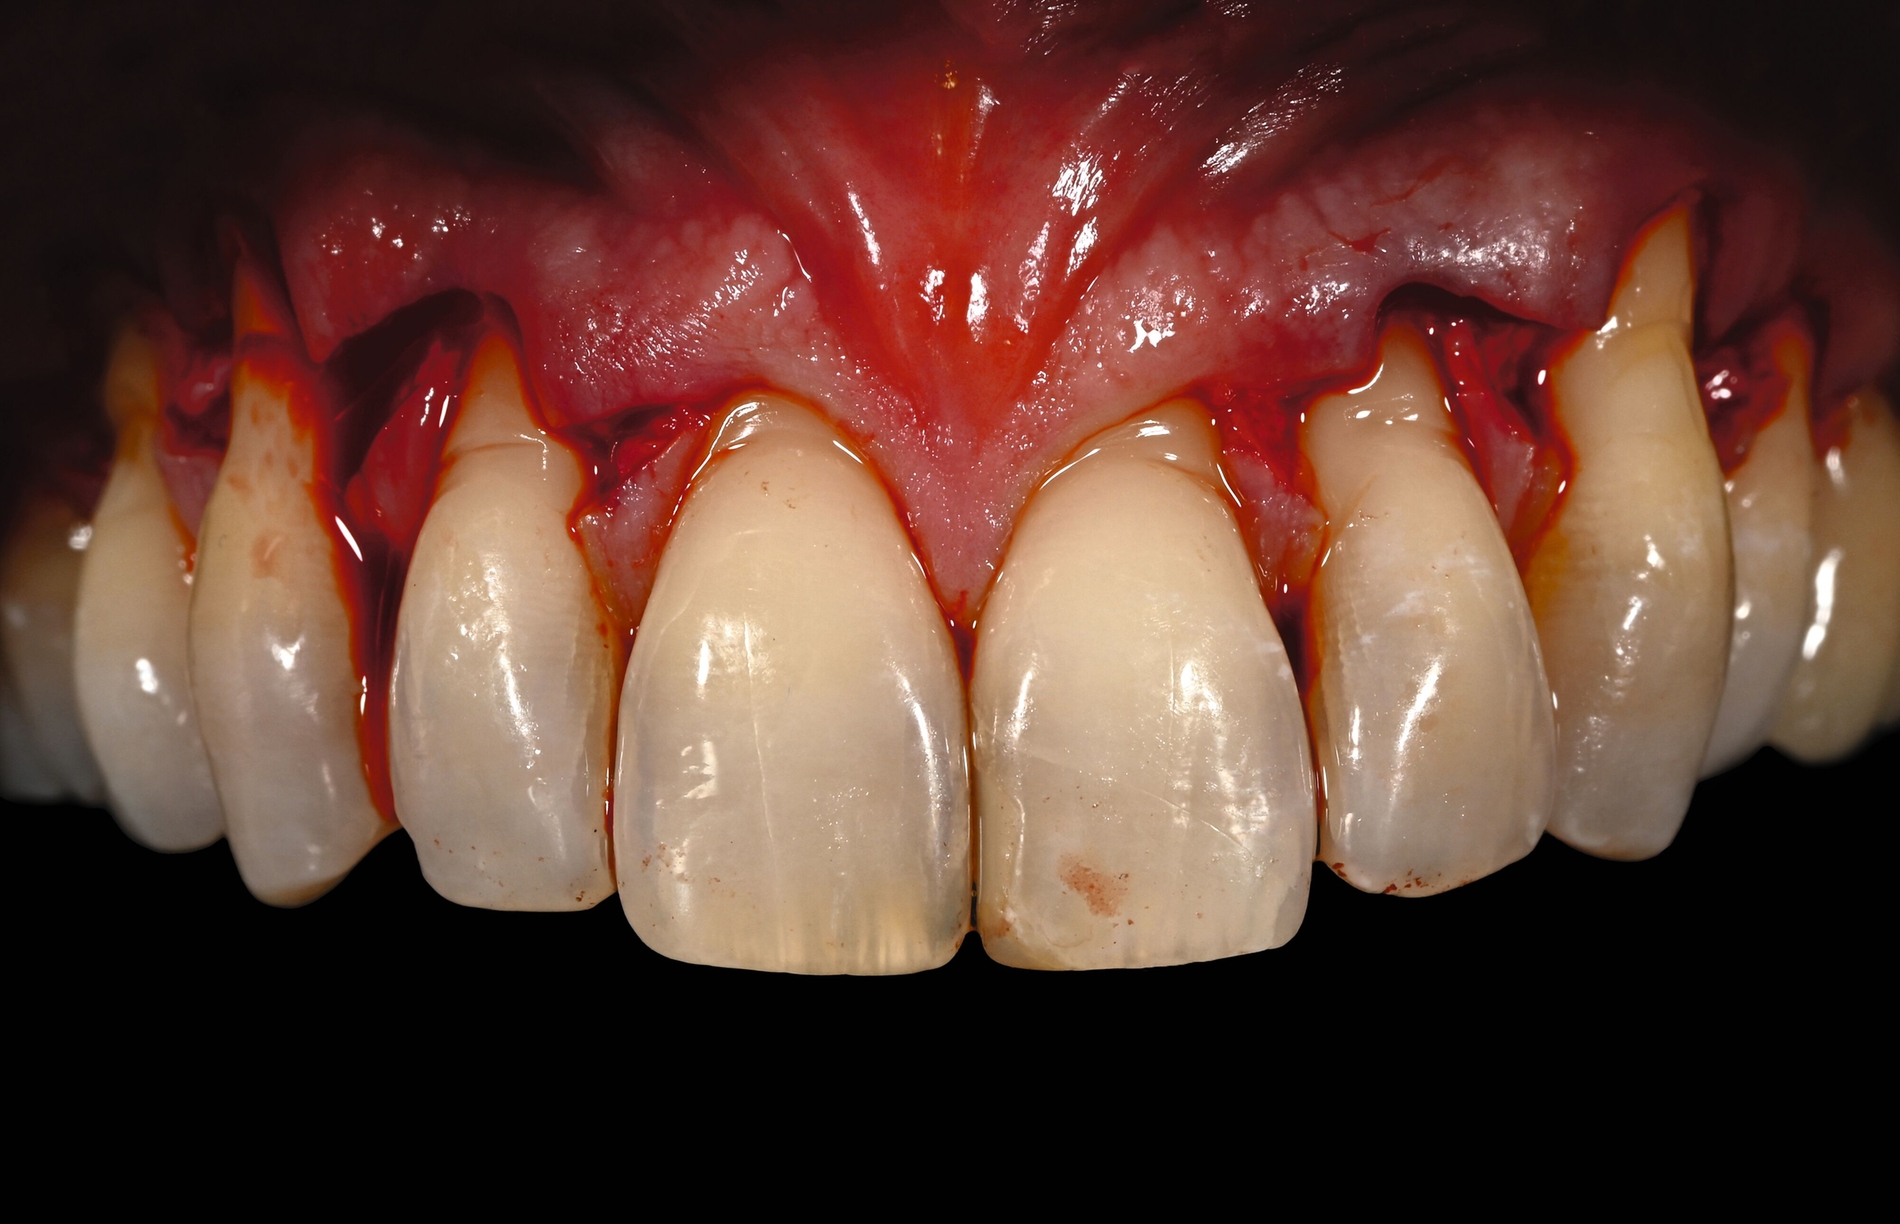

Trotz des Verbleibs des Epithels kann es zu sekundärer Wundheilung mit entsprechender Morbidität postoperativ kommen, besonders bei Techniken, die mehrere Inzisionen beinhalten, wie den sogenannten Trap-Door-Techniken, so dass sich die „Single-Incision-Technik“ durchgesetzt hat [Fickl et al., 2014]. Gegen eine übermäßige Blutung und postoperative Morbidität empfiehlt sich klinisch die routinemäßige Anwendung einer Verbandplatte, entweder in der Tiefziehtechnik oder präoperativ mittels eines Thermoplasts, so dass sich früh ein stabiles Blutkoagel bildet und die Wundheilung an der Entnahmestelle ungestört ablaufen kann. Dadurch wird die Morbidität klinisch deutlich reduziert. Das sBGT zeigt ästhetisch sehr gute Ergebnisse mit Blick auf Oberflächenstruktur sowie Farbe und kann unter anderem im Rahmen der Envelope- oder Tunneltechnik oder auch über einer Extraktionsalveole bewusst exponiert belassen werden, um zusätzlich befestigte Gingiva zu gewinnen.

Die Wundheilung nach dieser Technik erfolgt anders als beim sBGT immer sekundär, somit wurden bei Vergleichsstudien eine signifikant erhöhte Morbidität, Schwellungen und ein erhöhtes Nachblutungsrisiko beschrieben [Del Pizzo et al., 2002; Griffin et al., 2006], was jedoch bei entsprechender Versorgung des Gaumens umgegangen werden kann [Zucchelli et al., 2010]. Die Versorgung der Spenderregion kann mit Kollagenvlies, Cyanoacrylatkleber, Verbandplatte oder einer Kombination erfolgen. Dies kann die Morbidität deutlich reduzieren [Tavelli et al., 2019b]. Ein Vorteil von dBGT ist die Stabilität der Gewebedicke im Laufe der Zeit, was im Gegensatz zur beschriebenen Schrumpfung von sBGT steht, die häufig beobachtet wird [Zucchelli et al., 2018].